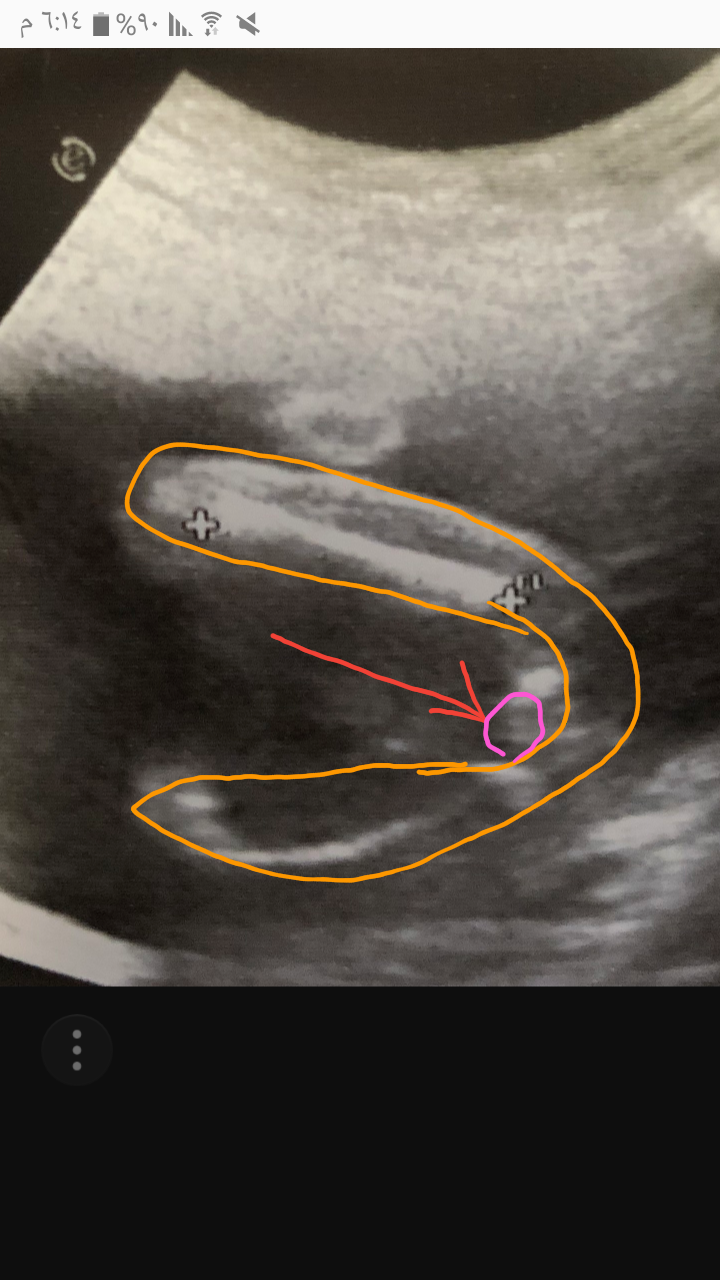

عزيزتي اللون البرتقالي عظمات الفخذ وهذه جلسة الجنين على شكلUكانه ماسك رجوله بيدينه السهم الاحمر مشار للحضو الانثوي والدائره الزهريه توضح الخطوط الثلاثه اثنين ابيض وهن الشفرات والاخط الاسود في المنتصف وهذا عضو انثوي. والله تعالى اعلا واعلم